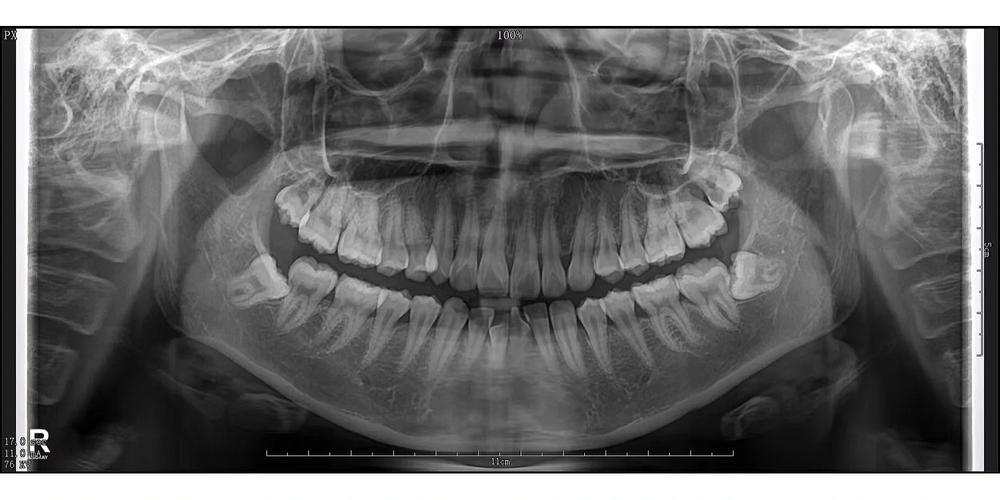

(图片来源网络,侵删)

- 治疗前、中、后的照片、X光片等影像资料。